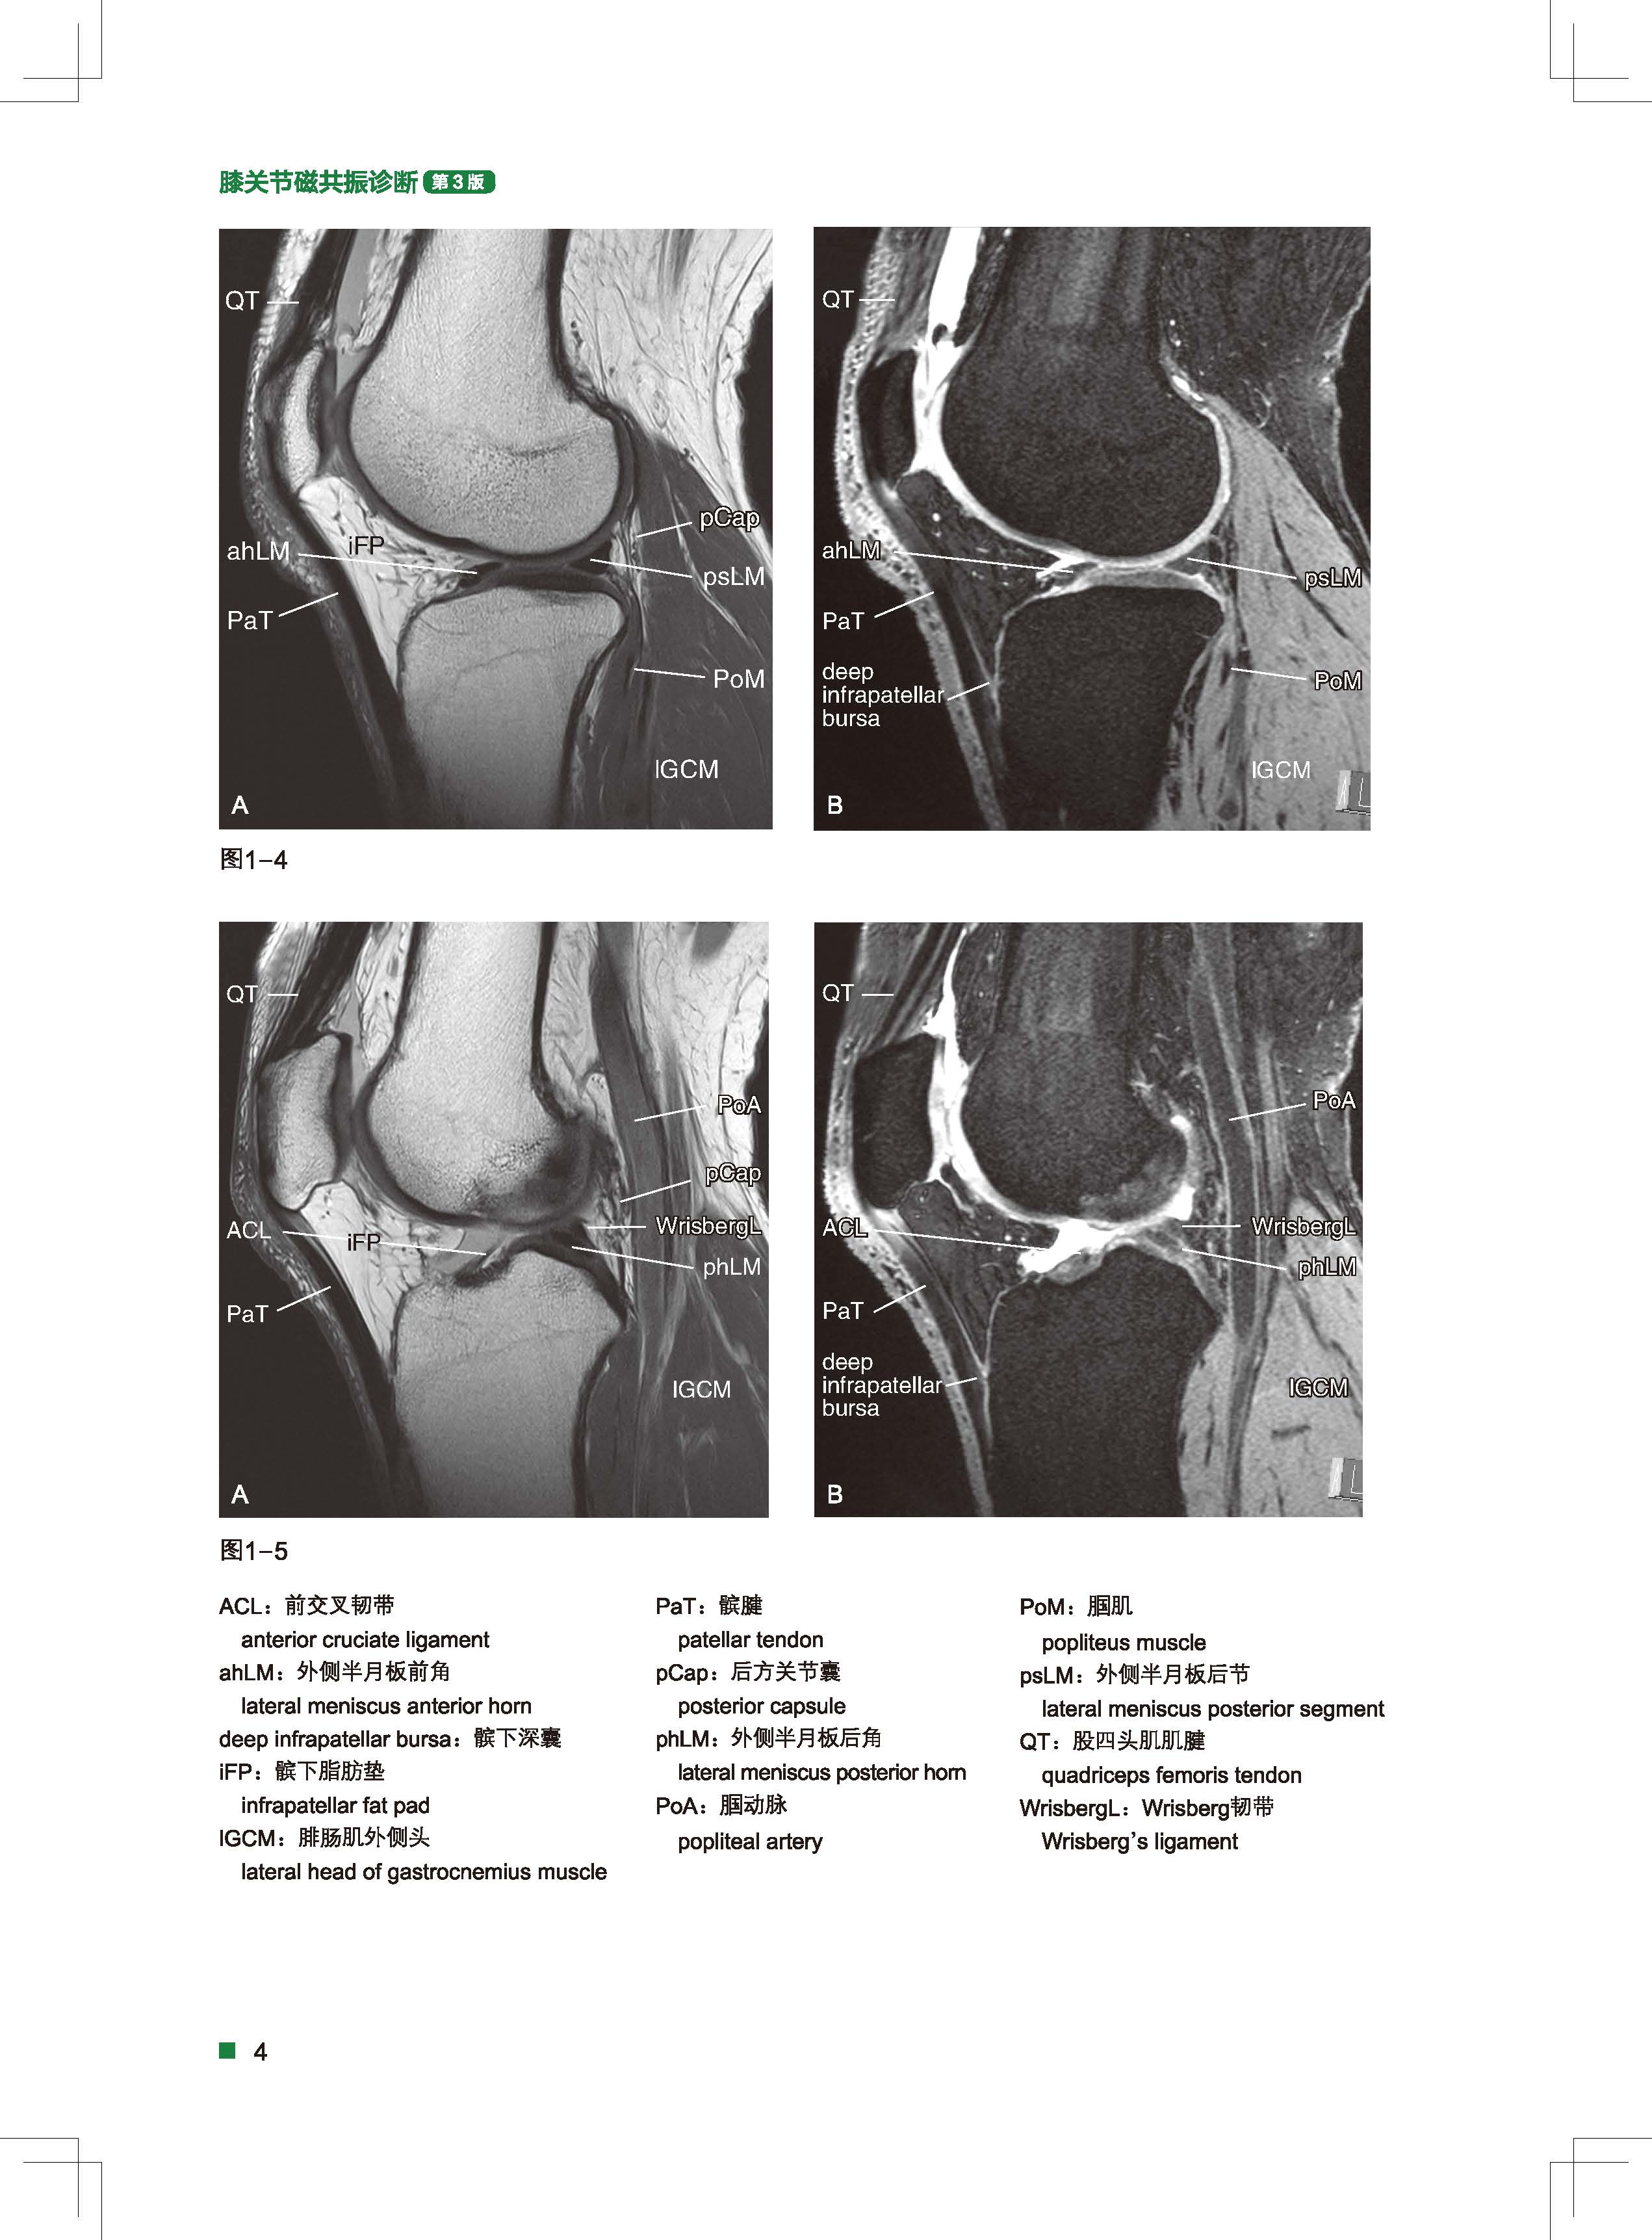

全书共分12章,第1-2章介绍膝关节各切面影像解剖,磁共振成像的各种方法;第3-7章分别介绍了前交叉韧带、后交叉韧带、包含内侧副韧带的内侧支持组织、包含外侧副韧带的外侧支持组织、半月板的解剖,磁共振图像,以及各种常见疾病的影像诊断要点;第8-12章分别介绍了骨折脱臼、肌肉损伤,青少年膝关节疾病,软骨损伤、变形及坏死,滑膜病变与皱襞功能障碍,膝关节内外积液5类疾病中各种问题的影像诊断。